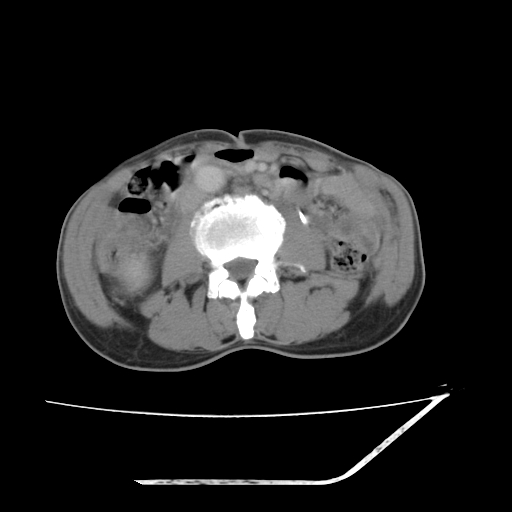

增强

考虑右肾盂癌,肾动脉受侵,右肾功能减退,右肾盂输尿管积水,管壁增厚,考虑种植转移,应该把下面扫完的

支持右侧肾盂癌伴肾静脉瘤栓形成可能性大,右肾结石.肝右叶后段低密度影,不除外转移.

右肾盂旁ca并肾静脉瘤栓形成/肾功能降低。

右肾结石。

右肾盂癌,肾动脉受侵,右肾盂输尿管积水,管壁增厚,考虑种植转移

右肾盂移行细胞癌并右输尿管中段转移.肾积水.

1.右侧肾盂癌伴肾盂积水。

2.肾脏功能减退,原因有:(1)肾动脉受侵。(2)肾静脉受侵(3)肾积水,等。本例,肾动脉显影较好,但受压明显;肾静脉无明显显示,受压或静脉癌栓,下腔静脉腔内未见明显充盈缺损。

3.右侧上段输尿管扩张,原因:(1)积水所致;(2)种植。